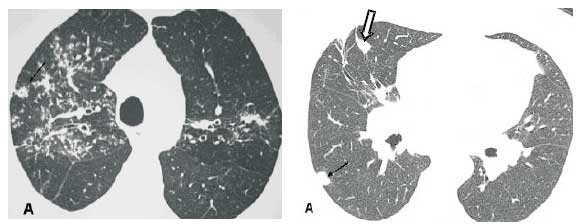

Nódulos. O padrão nodular é o mais freqüente na sarcoidose pulmonar. Os nódulos são geralmente pequenos e apresentam uma distribuição perilinfática, com envolvimento dos feixes peribroncovasculares, septos interlobulares, regiões centrolobulares subpleurais e ao longo das fissuras (Figuras 1 a 3). Nódulos cavitados ou de grandes dimensões, por vezes simulando neoplasias, podem ser encontrados em 15% a 25% dos casos (Figura 4)(1,4,7-10).